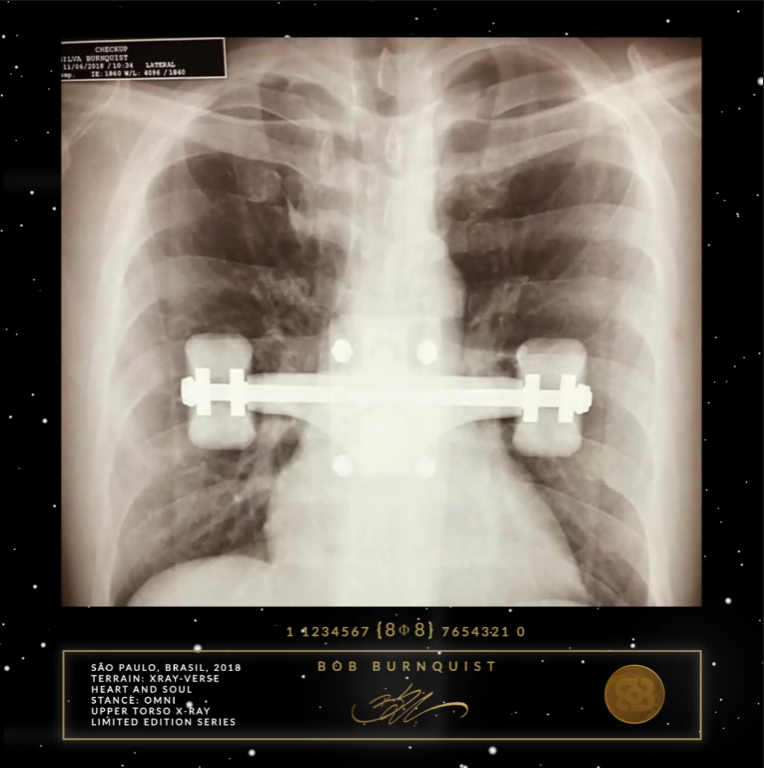

Sonhos e ossos quebrados. É uma luta dolorosa e alegre. Todo o esforço, amor e paixão valem a pena. Momentos se tornam eternos. Criar é uma oração de gratidão ao Criador. Quando fecho os olhos, posso viver e sentir os trucks ( ou eixos são peças de metal que ficam encarregadas de fazer as curvas do skate na direção em que se inclina o corpo.) que consegui ao longo dos anos. Alguns deles desembarcaram apenas uma vez. Manifestado para sempre.

Somos crianças douradas em uma era dourada com um propósito dourado. E este é o meu dent digital no universo.